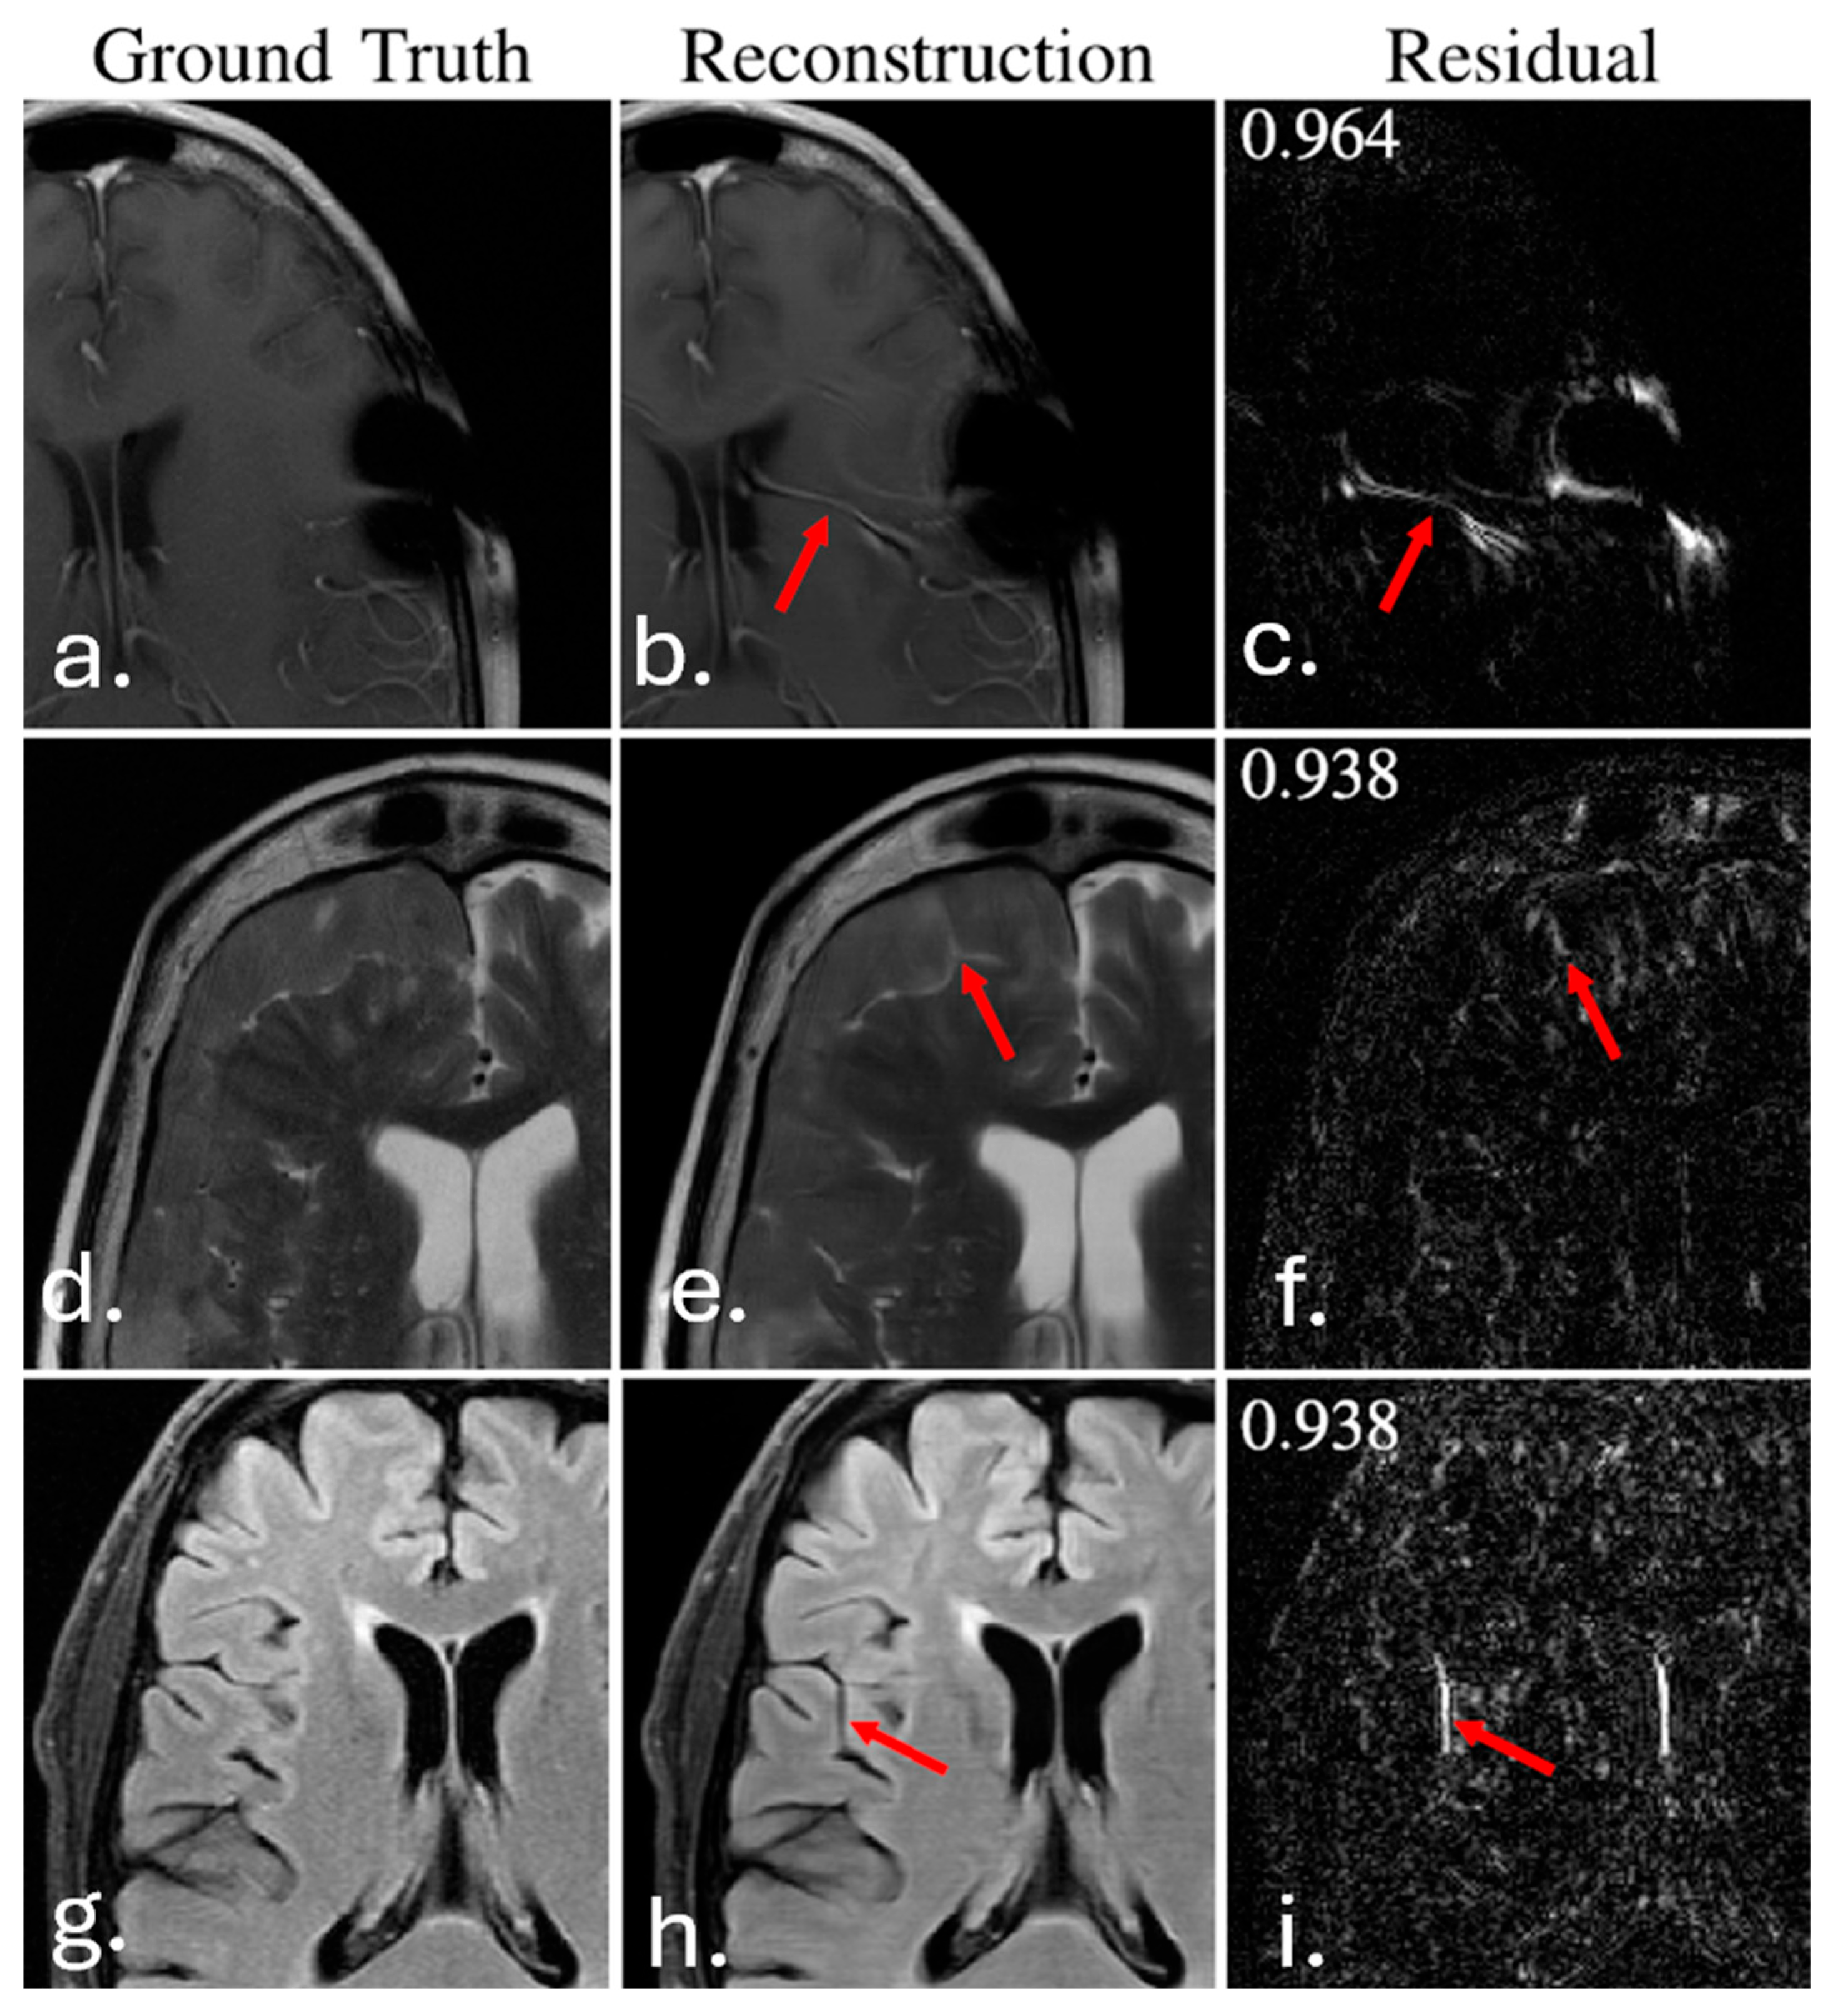

| MRI reconstruction | Accelerated image reconstruction | fastMRI challenge (Knoll et al., 2020, Muckley et al. 2020) [96,97] | Multivendor MRI datasets | SSIM often > 0.95; localized hallucinations reported | High quantitative image quality; hallucinated or missing structures preclude unsupervised clinical use |

| MRI | Accelerated image reconstruction | Deep learning reconstruction networks | SSIM > 0.95; PSNR improvement reported | High quantitative image quality, with a documented risk of hallucinated or missing structures |

| MRI image reconstruction | MRI | Deep learning reconstruction networks | Knoll et al., 2020; fastMRI [96] | SSIM often > 0.95 | Risk of hallucinated or missing anatomical structures |